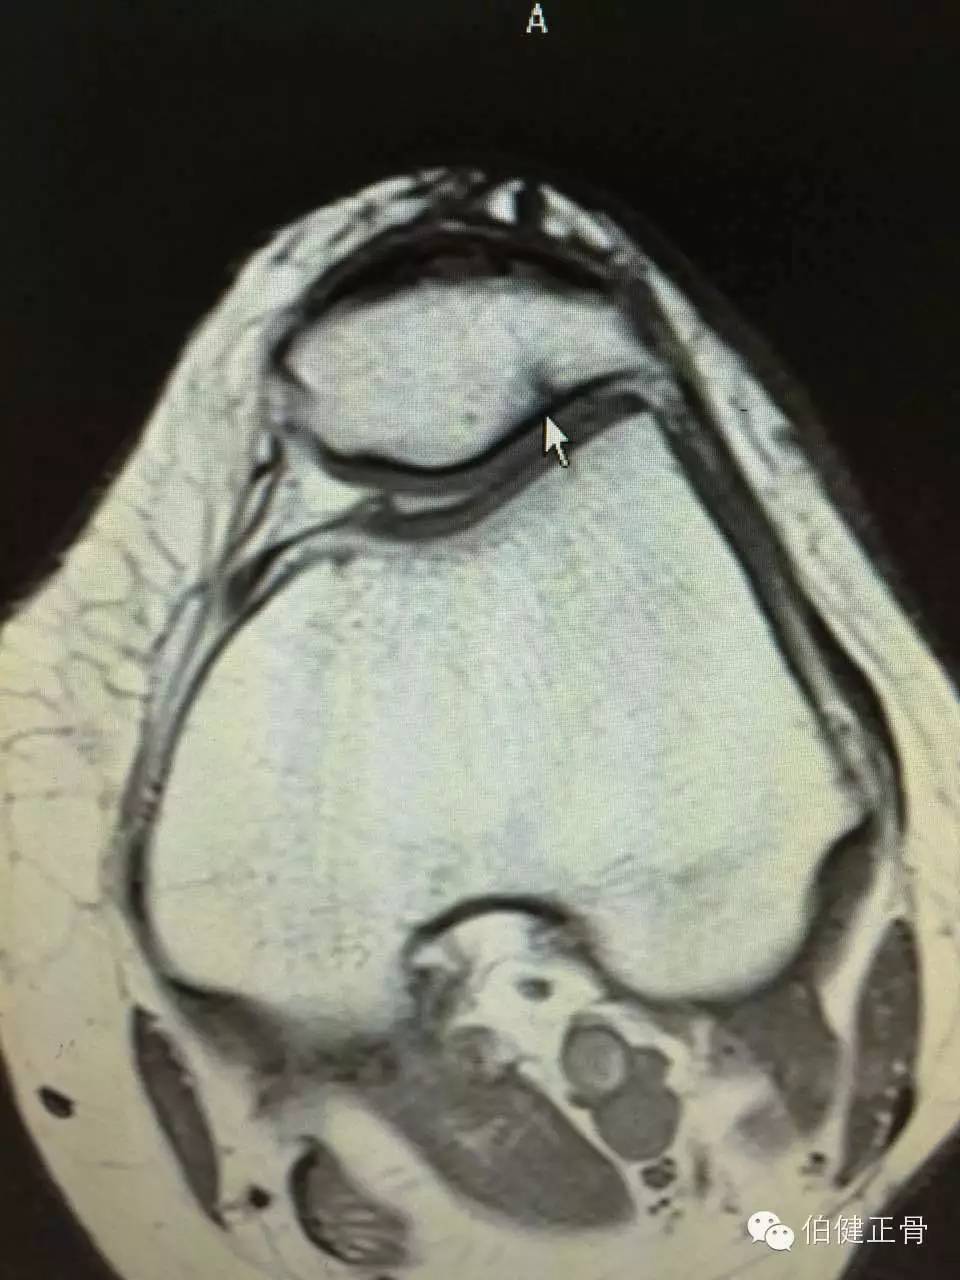

附髌骨软化症的诊断:

3.X线检查:照膝关节正,侧位及髌骨切线位X线片,早期无异常所见,晚期可因软骨大部磨损,髌骨与股骨髁部间隙变窄,髌骨和股骨髁部边缘可有骨质增生。

诊断髌骨软化症的主要依据是髌骨后的疼痛,髌骨压磨试验和单腿下蹲试验引起髌骨后疼痛,应该注意检查有无合并半月板损伤和骨关节炎等。